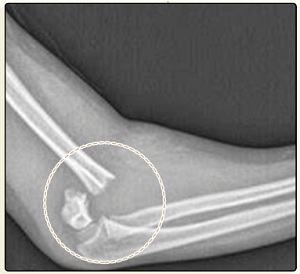

人的上臂骨骼

有一个很脆弱的点

大概就是这里

掰手腕的错误发力

可能会像拧瓶盖一样

咔的一声把这个地方拧碎

造成肱骨踝骨折

而且手臂长的人

会比手臂短的人

骨折风险更高